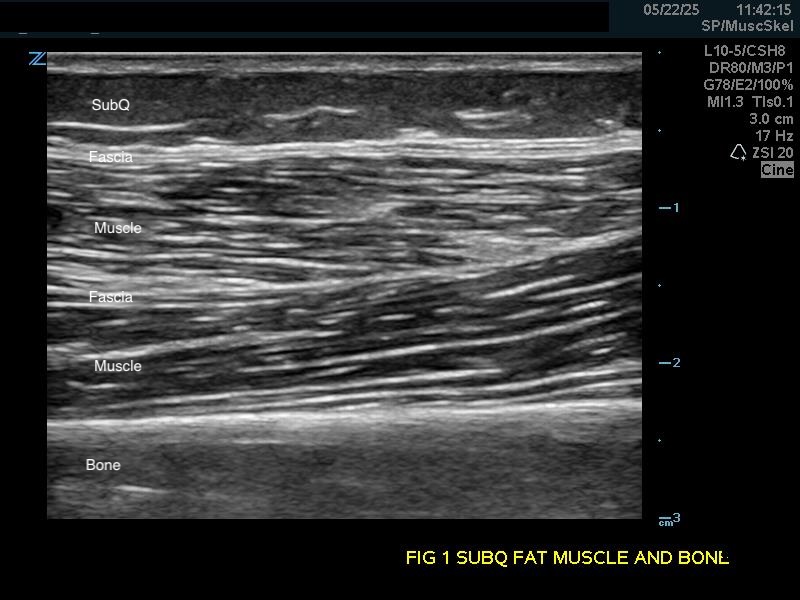

Figure 1a.

(A) Longitudinal view. Bone appears as a distinct bright echogenic line with no visible structures beneath, Subcutaneous fat appears relatively hypoechoic with thin septations of connective tissue.

Subcutaneous fat: Relatively hypoechoic with thin septations of connective tissue. The thickness of this layer varies and may require increasing the depth setting of your machine.

Muscle: Longitudinally, appears as slabs of striated hypoechoic tissue contained within the thin hyperechoic lines of fascia. Viewed transversely, muscle striations or septa appear dotted and punctate or form short lines. Fascial lines separate muscle compartments.